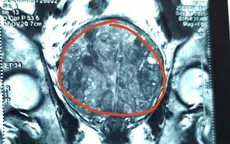

Ngã chấn thương sọ não, vào viện bất ngờ phát hiện khối u não kích thước lớn

VTV.vn - Bệnh viện Đa khoa tỉnh Quảng Ninh vừa phẫu thuật vi phẫu bóc tách thành công khối u não kích thước lớn cho một ca chấn thương sọ não.